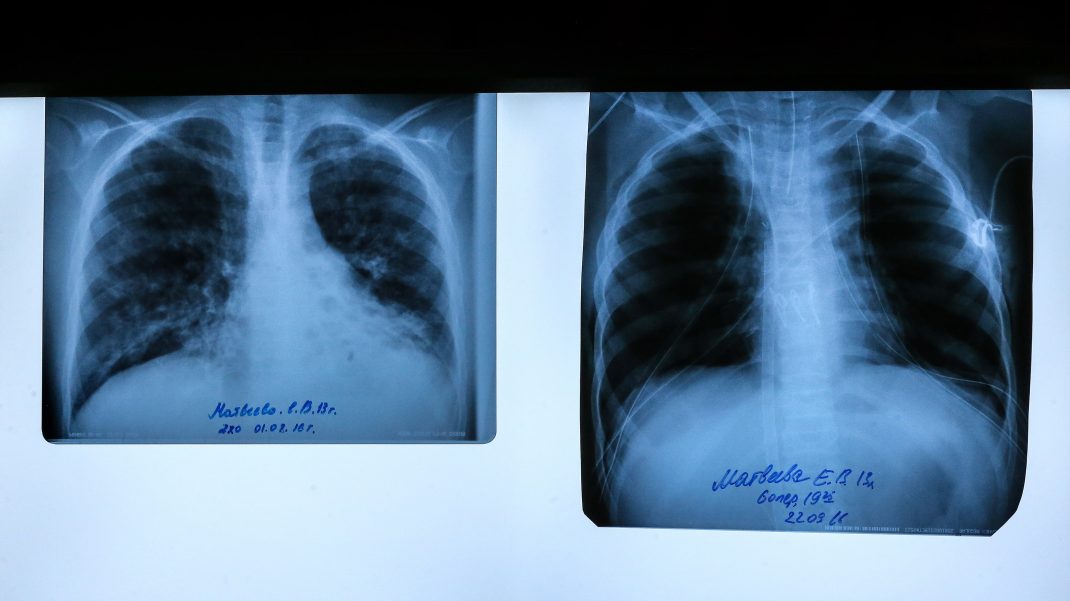

Фото: Валерий Шарифулин / ТАСС

Муковисцидоз — генетическое заболевание, при котором поражаются органы внешней секреции и дыхательная система. Представители благотворительных фондов рассказывали «Медузе», что компаниям, производящим подобные лекарства, невыгодно завозить их в Россию из-за политики импортозамещения — они проигрывают конкуренцию отечественным компаниям. В то же время средняя продолжительность жизни пациентов с муковисцидозом в США — 40 лет, в России — около 25 лет.